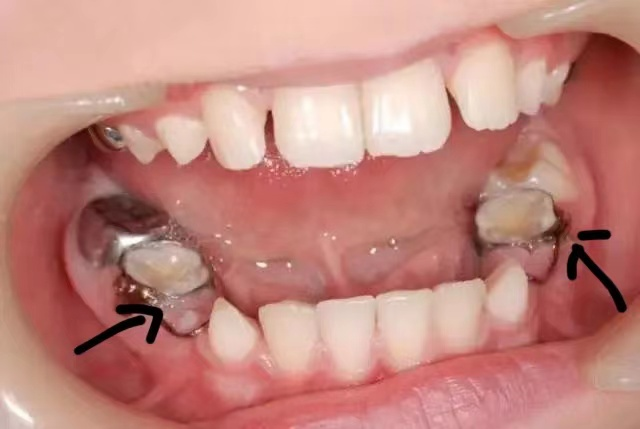

6.乳牙早失

(箭头指的是间隙保持器)

乳牙还没到替换时间就过早脱离,会使局部颌骨发育不足,缺牙的位置可因邻牙移位导致部分甚至全部被占据,以致恒牙错位萌出或埋伏阻生而形成牙颌畸形,对于早失的牙齿需要制作间隙保持器维持间隙等待恒牙萌出。